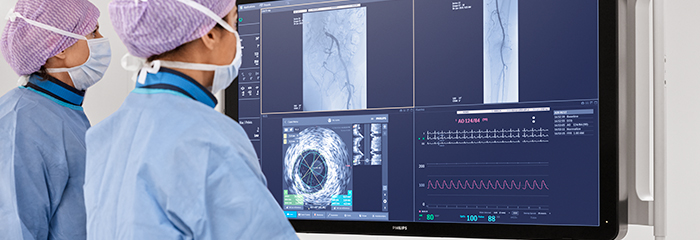

Image-guided therapy, iFR, IVUS and hemodynamic monitoring, as well as cardiac pre-procedure planning and advanced applications, are all connected to the image-guided therapy interface to allow viewing, manipulation, and custom configuration on the monitor from a single controller at table side or from the control room.

Interventional Applications Workstation — IntraSight

Provides more comprehensive clinical insights with seamless integration of iFR/FFR, IVUS and co-registration tools that improve patient health outcomes.You are about to visit a Philips global content page

IntraSight

The IntraSight Interventional Applications Workspace is where imaging, physiology, co-registration* and software all come together to clearly identify coronary and peripheral artery disease, and allow for more optimized treatment plans. IntraSight is built on a new foundational platform designed to meet the evolving needs of your lab today and tomorrow.

Dynamic Coronary Roadmap

Dynamic Coronary Roadmap, a Philips-exclusive technology, creates a motion-compensated, real-time view of coronary arteries. Recent evidence demonstrates that DCR can reduce contrast agent by 28.8% during a PCI procedure. With DCR a highlighted coronary angiogram is superimposed on a live 2D fluoroscopic image, creating a colored roadmap that adjusts automatically, providing continuous visual feedback on positioning of wires and catheters.

Hemo with IntelliVue X3

Improving productivity and outcomes is vital for healthcare facilities to meet the growing demand for cath lab procedures. To further simplify cath lab workflow, Philips introduces the Interventional Hemodynamic system (Hemo system) which brings advanced hemodynamic measurements to the cath lab. Integration with the IntelliVue X3 patient monitor helps to enable confident clinical decision making and gap-free patient medical records, continuously monitoring the patient in the cath lab or extended throughout the hospital.